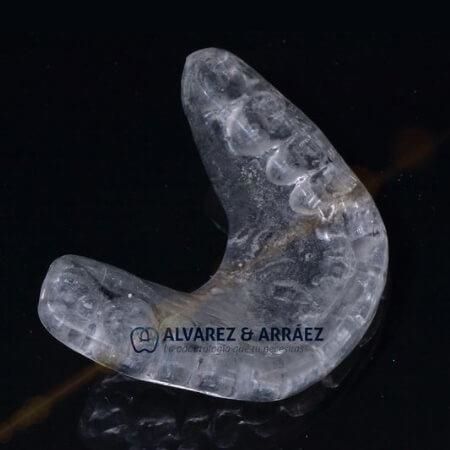

Servicios y tratamientos:

Tecnología: